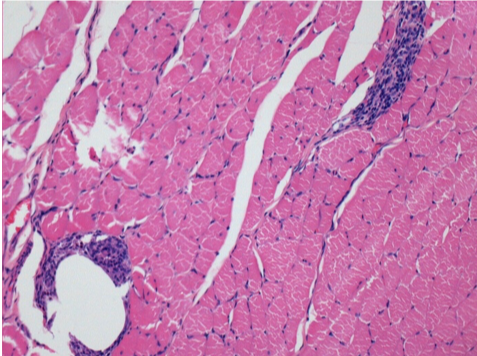

1 mese dopo Iniezione Endopeel

Scatola Nr 3

1 mese dopo Iniezione 0.1ml di Endopeel nel muscolo pretibiale destro ( Dx) .

Che cosa viene visualizzato in nero nella figura Sx : 100x-Giorno30 non é una necrosi come potrebbe immaginare un dilettante.

In effetti, 4 conclusioni devono essere prese in considerazione

- un artefatto di colorazione

- un`assenza di necrosi

- un`apoptosi

- un processo biorigenerativo

Sx : Controllo-100x-Giorno30

Dx:100x-Giorno30

Dx :400x-Giorno30